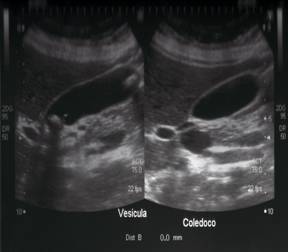

Al día siguiente de hospitalización se solicita exámenes de imagen tales como ecografía abdominal donde se observa hígado normal, con vesícula distendida, con paredes lisas, con pólipo en su interior y colédoco libre. Ecografía del cuello reporta una glándula tiroidea con presencia de un nódulo con micro–calcificaciones en lóbulo derecho (Figuras 1-4).

La valoración por especialista en Neurología, concluye con la petición de Tomografía Axial de Cráneo, debido a vértigo y cefalea frecuente, obteniendo un informe radiológico normal. Se realiza una RX estándar de tórax con resultado normal y un electrocardiograma el cual resulta con trazo normal. Subsecuentes análisis de sangre reportan factores de coagulación normales, y serología para Hepatitis A, B, C con resultado negativo. La paciente es estabilizada y durante el segundo día de hospitalización se siguiere administración de Levotiroxina 50 mcg vía oral cada 24 horas. Luego en horas de la tarde se practica Colecistectomia Laparoscópica por su pólipo vesicular, cuyo período postoperatorio inmediato transcurrió sin complicaciones. Se da de alta al 4to día en mejor condición clínica y controles endocrinológicos en las siguientes semanas por su sintomatología de hipotiroidismo. El tratamiento ambulatorio incluyó analgésicos, antibiótico profilaxis por la colecistectomía laparoscopica, Levotiroxina 50mg vía oral al día, dieta rica en fibras, y tratamiento con Atrovastatina 10mg diarios para hipercolesterolemia. A la siguiente semana, la paciente acude a control en mejores condiciones clínicas, trayendo exámenes control que se describen en Tabla 2. Finalmente se añade a su tratamiento Fluoxetina 50mg por valoración de médico psiquiatra bajo impresión diagnostica de depresión moderada, enzimas digestivas y protectores hepáticos, y betahistidina clorhidrato 16mg vía oral cada 12 horas por 15 días. Se solicita laboratorio pertinente para ETAI, Anticuerpos anti TPO y ANA HEP para la próxima valoración clínica (Tabla 3).